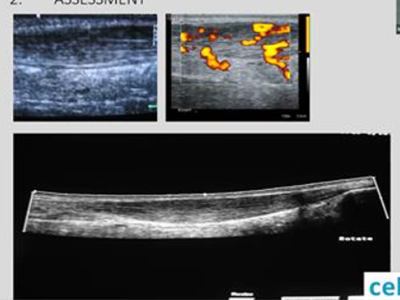

Diagnostic Ultrasound Workshops at Therapy Expo 2023

Therapy Expo|22nd and 23rd November 2023 | NEC, Birmingham

Do you know how to scan the plantar plate?

Our mentoring courses are proving very popular. Keep your eyes peeled for the next course so you don’t lose out.

Diagnostic Ultrasound Scanning Webinar Series

Read more about our 3 part webinar series